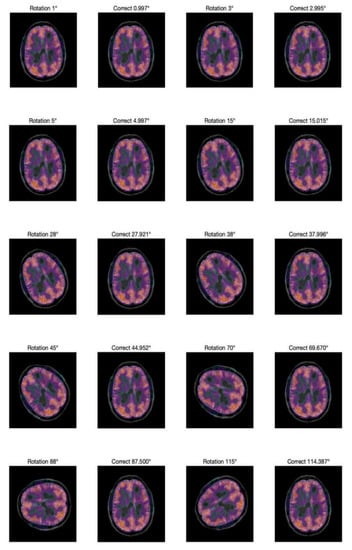

The two-phase values are recorded at (1, −1), (2, −2). Figure 5 compares of the image before and after correction at different rotation angles.

Figure 5.

Comparison of the image before and after correction.

To compare the results with those reported in [37], the same rotation angle is used. The results of the experiment show that the Zernike moments have a strong detection ability for a rotation attack, especially for small-angle rotations: the error can be less than 0.005 degrees.

To explore the correction ability of this scheme for small angle rotation, a more detailed experiment is performed on rotation at small angles, which are less than 3 degrees. The results are shown in Figure 6. Note that this scheme has good correction ability for small angle rotation.

Figure 6.

Rotation and correction at small angle.